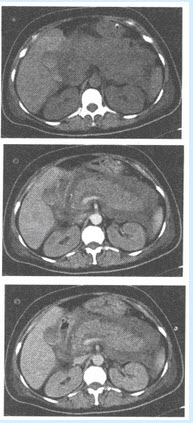

(单选题)患者所做CT图像如下,应考虑哪种疾病()

B:胰腺外形增大,密度不均,边界模糊,与周围组织分界不清

C:胰腺周围有少量水样低密度影

E:肾周筋膜增厚